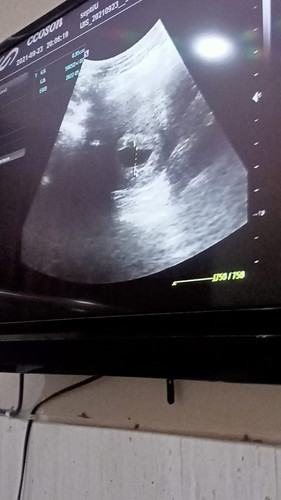

Bund saya mau tanya, saya harusnya kalau dri hitungan di puskesmas udah hamil 9minggu tp pas usg ternyata usia kehamilan saya turun jdi 5minggu. Awal usg masih belum kelihatan kantongnya, di suruh balik lgi 2minggu kemudian. Kemarin tgl 23 saya balik usg, ternyata cuma kelihatan kantongnya aja, dan dokter lgsg bilang kalo janin saya gak berkembang. Di suruh balik lgi seminggu kemudian. Menurut bunda, apa emang kalo usia 5 atau 6 minggu baru kelihatan kantong nya aja ya? Apa gimana bun? Saya takut dan bingung, kalo seminggu kemudian masih tetep cuma keliatan kantong dan dokter masih bilang gak berkembang saya harus kuret Dan kemarin sempet di ajakin bude ke dukun bayi, di elus2 perut saya katanya ada kok bund bayinya tp emang kandungan saya lemah. Saya jadi makin kepikiran bund. Saya harus gimana yaaa 😔 #pleasehelp #bantusharing